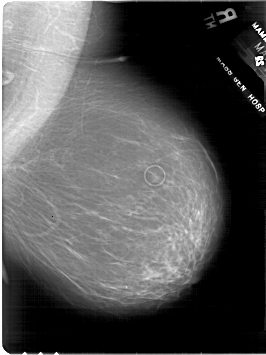

A_1801_1.RIGHT_CC

RIGHT_CC LINES 6196 PIXELS_PER_LINE 4396 BITS_PER_PIXEL 12 RESOLUTION 43.5 NON_OVERLAY